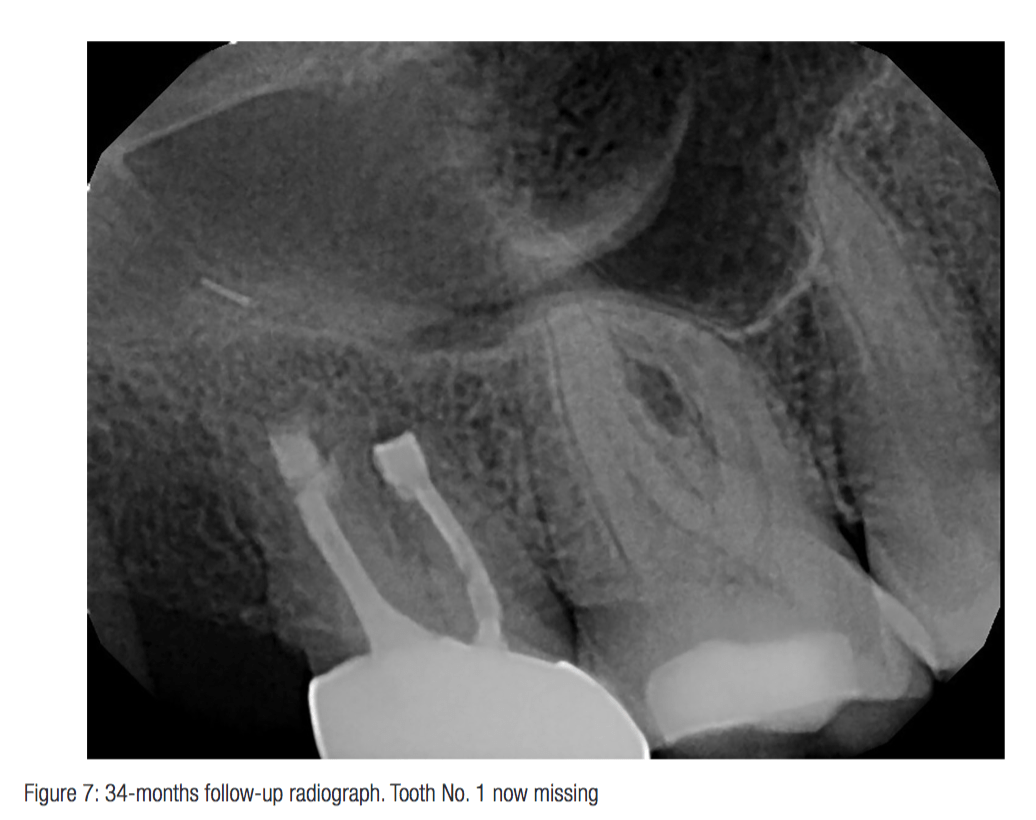

Endodontic Replantation. surgical extrusion, intentional replantation and tooth autotransplantation are. what was once thought of as a procedure of last resort, replantation is a procedure that has been performed successfully for decades, with a success rate just reported in the december 2017 issue of the journal of endodontics of 89.1 percent. Details of reported and advocated techniques in the endodontic literature are demonstrated in both text and. intentional replantation, a type of autotransplantation, is an endodontic procedure that involves intentional extraction of the. Intentional replantation is a clinical technique used by endodontists routinely throughout the world to treat disease of endodontic origin. introduction intentional replantation (ir) may offer a solution for persistent periapical lesions associated with. surgical extrusion, intentional replantation and tooth autotransplantation are. the primary purpose of endodontic treatment is to cure pulpal and periapical pathosis. This article provides a critical review of the reported and suggested techniques, highlighting differences and consistencies.

surgical extrusion, intentional replantation and tooth autotransplantation are. intentional replantation, a type of autotransplantation, is an endodontic procedure that involves intentional extraction of the. Intentional replantation is a clinical technique used by endodontists routinely throughout the world to treat disease of endodontic origin. Details of reported and advocated techniques in the endodontic literature are demonstrated in both text and. what was once thought of as a procedure of last resort, replantation is a procedure that has been performed successfully for decades, with a success rate just reported in the december 2017 issue of the journal of endodontics of 89.1 percent. the primary purpose of endodontic treatment is to cure pulpal and periapical pathosis. surgical extrusion, intentional replantation and tooth autotransplantation are. introduction intentional replantation (ir) may offer a solution for persistent periapical lesions associated with. This article provides a critical review of the reported and suggested techniques, highlighting differences and consistencies.

Endodontic Replantation surgical extrusion, intentional replantation and tooth autotransplantation are. surgical extrusion, intentional replantation and tooth autotransplantation are. intentional replantation, a type of autotransplantation, is an endodontic procedure that involves intentional extraction of the. This article provides a critical review of the reported and suggested techniques, highlighting differences and consistencies. introduction intentional replantation (ir) may offer a solution for persistent periapical lesions associated with. Details of reported and advocated techniques in the endodontic literature are demonstrated in both text and. surgical extrusion, intentional replantation and tooth autotransplantation are. what was once thought of as a procedure of last resort, replantation is a procedure that has been performed successfully for decades, with a success rate just reported in the december 2017 issue of the journal of endodontics of 89.1 percent. Intentional replantation is a clinical technique used by endodontists routinely throughout the world to treat disease of endodontic origin. the primary purpose of endodontic treatment is to cure pulpal and periapical pathosis.